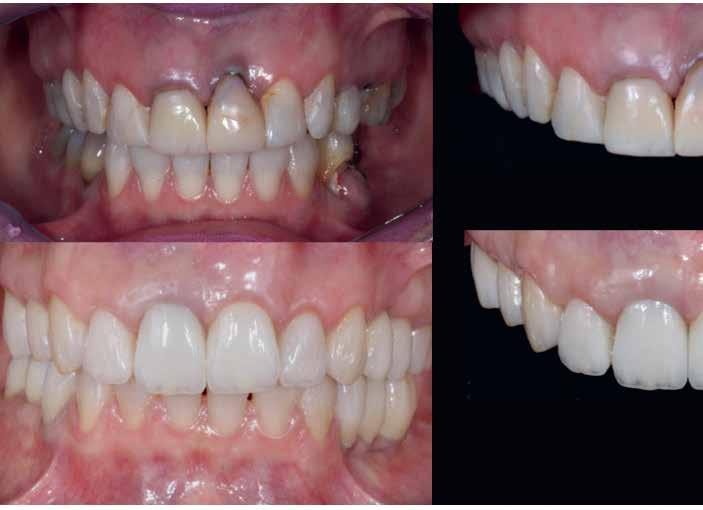

A front régióban alkalmazott minimál invazív multidiszciplináris megközelítés eredményeként jelentős mértékben tudtuk javítani a páciens esztétikai megjelenését. A beavatkozások során japán washi papír felhasználásával történő belső fogfehérítést, valamint háromdimenziós nyomtatással készült sebészeti sablon által vezetett ínyplasztikát végeztünk, majd az esztétikai zónában lévő fogakat – köztük egy elszíneződött nagymetsző fogat – ultravékony földpátkerámia héjakkal láttuk el.

A páciens elsősorban a mosolyának megjelenésén szeretett volna javítani. Egy előzetes állapotfelmérést követően az elszíneződött fog belső fehérítését, ínyplasztikát, valamint a felső front- és első kisőrlőfogak esztétikai célú helyreállítását javasoltuk. A belső fogfehérítés során nátrium-perborát és 30%-os hidrogén-peroxid keverékével átitatott washi papírt alkalmaztunk. Az anyag pulpakamrába történő helyezését követően az üreget üvegionomer cementtel zártuk. A fogfehérítés befejezését követően 3D nyomtatott sebészi sablont készítettünk, majd a felső front régióban megfigyelhető lágyrészek lefutását ezen sablon segítségével korrigáltuk. A sebészi beavatkozást követően 6 hónappal ultravékony földpátkerámia héjakat készítettünk.

A rendelésünkön jelentkező 40 éves nőbeteg a mosolyának esztétikai megjelenésén szeretett volna javítani (1. ábra)

A vizsgálat során a jobb felső első kisőrlőfog (1,4) és a bal felső első kisőrlőfog (2.4), valamint a köztük elhelyezkedő fogak kifejezett mértékű kopását észleltük (14-24). Ezen felül a felső metszőfogak (1.2–2.2) élei egyenetlen lefutással rendelkeztek, és a jobb felső nagymetszőfog (11) – amelyet korábban gyökérkezeltek és kompozit töméssel láttak el –jelentős színbeli eltérést mutatott. Az 1.4-es és 2.4-es fo-

A belső fogfehérítés utáni állapot.

gak között mért tasakmélység mértéke sehol sem haladta meg a 3 mm-t. A páciens számára belső fogfehérítést, ínyplasztikát és kerámia héjak készítését javasoltuk. A páciens a felajánlott kezelési tervet elfogadta. Első lépésként az 1.1es fog belső fogfehérítését terveztük, mivel a későbbiekben ezt a fogat is kerámia héjjal akartuk ellátni.

A páciens elégedett volt a végleges restaurátumok színével, formájával és méretével. A kezelés végeredménye kielégítette az esztétikai elvárásait (9. ábra). A frissen átadott restaurátumok épségének megőrzése érdekében a páciens számára éjszakai fogvédősínt készítettünk. A páciensünk a négyéves kontrollvizsgálat során is nagyon elégedett volt a kezelés eredményével. A korábban meglévő fekete háromszögek eltűnésének különösképpen örült (9. és 10. ábrák)

9. ábra. A beavatkozás után, valamint a 4 évvel később látható állapot. (A): Egy héttel a ragasztás után készült felvétel. (B): A négyéves kontroll alkalmával készült felvétel.

Jelen esettanulmányban három meglévő technika kombinálását és továbbfejlesztését mutattuk be: washi papír használatával történő belső fogfehérítést, nyomtatott sebészi sablon által vezetett ínyplasztikát, és a fogakra ultravékony földpátkerámia héjakkal történő ellátását. E bonyolult eset kezelése során – minimálinvazív megközelítés mellett – kiemelkedő esztétikai eredményt sikerült elérni.

Az alapos tervezést követően végzett restauratív beavatkozások során sikeresen kombináltuk a washi papírral végzett belső fogfehérítést, a 3D nyomtatott sebészeti sablonnal és elektrokauterrel végzett ínyplasztikát, továbbá az ultravékony földpátkerámia héjakkal történő ellátást. A kezelési terv követésével el lehetett érni a kívánt esztétikai eredményeket, amelyek már 4 éve stabilnak bizonyultak.